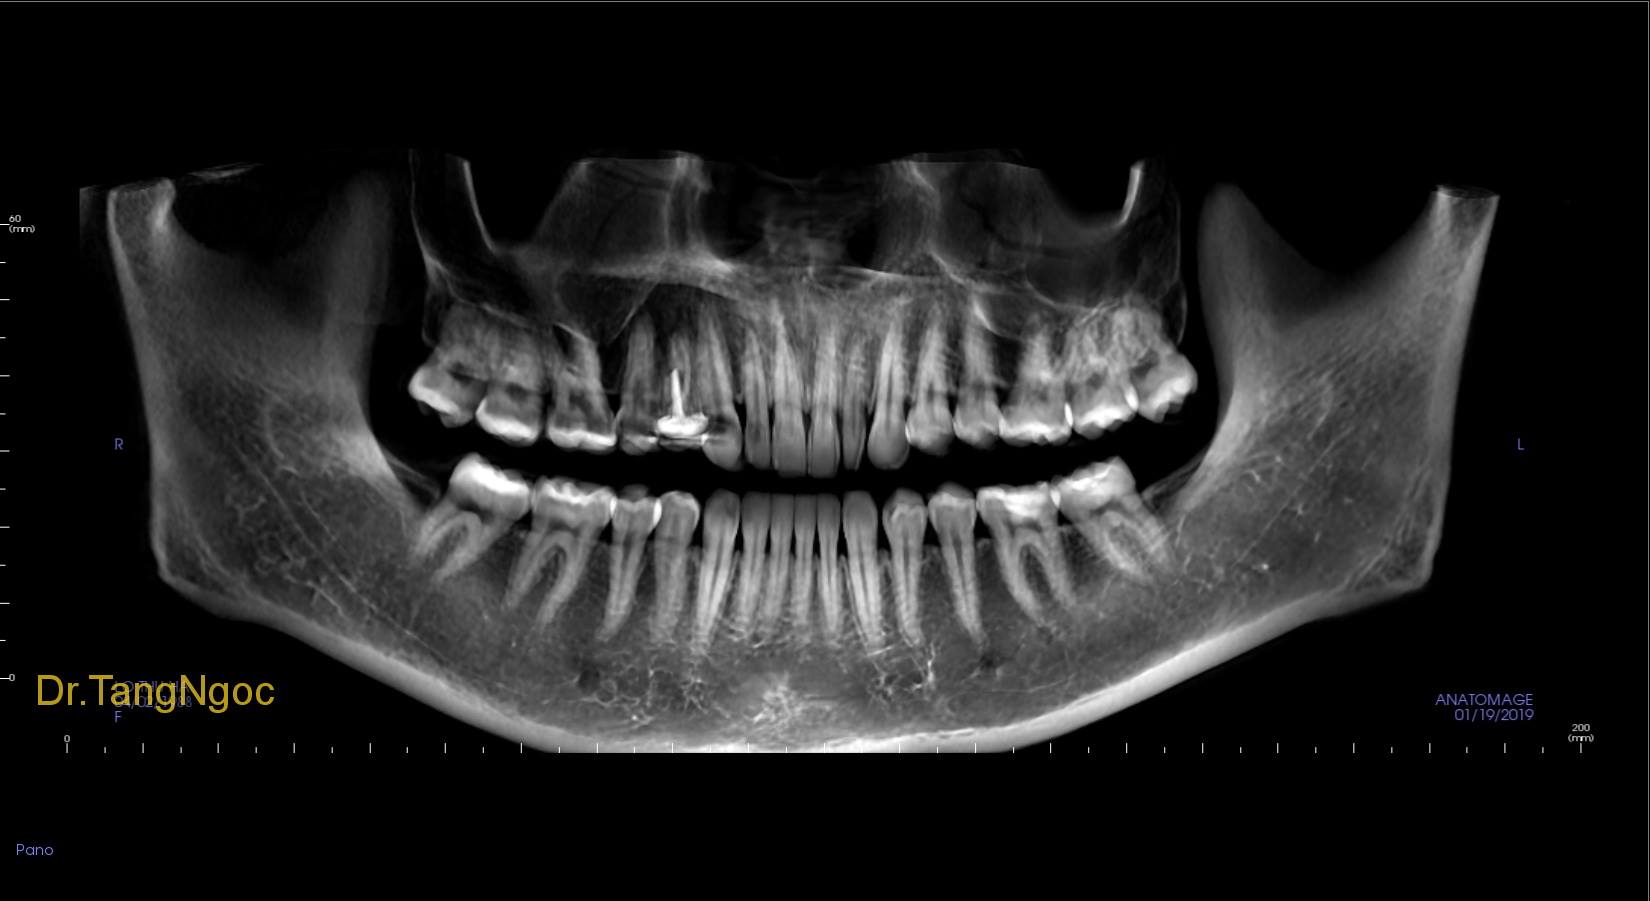

- Độc tố từ vi khuẩn trong cao răng sẽ gây phản ứng viêm như viêm nha chu, tiêu xương ổ răng làm cho lợi mất chỗ bám, chân răng lộ ra, không được các tổ chức xung quanh bảo vệ, lâu dần sẽ dẫn đến răng lung lay hoặc mất răng.